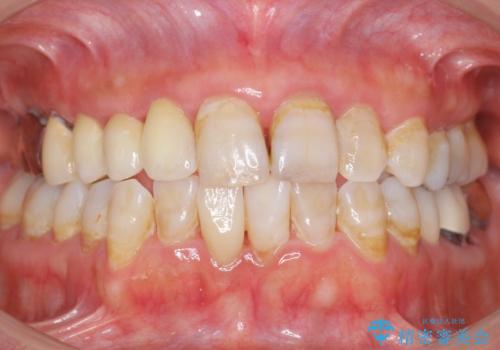

ブリッジとクラウンの自然な仕上がりと咬み心地に喜んで下さいました。

精密な根管治療により、下の前歯の歯ぐきにできていた瘻孔もなくなりました。

短期間(2ヶ月)でしっかりとした治療が受けられたとご満足頂けました。

右上④3②ブリッジ:オールセラミッククラウン スタンダード

右下1クラウン:オールセラミッククラウン エコノミー